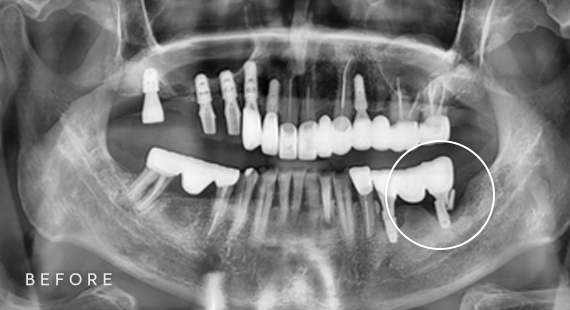

임플란트